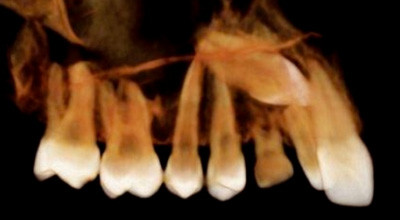

Mit der digitalen Volumentechnologie (DVT) wurde erstmals 1998 eine neue Aufnahmetechnik in die Zahnmedizin eingeführt, die der CT vergleichbare Darstellungsmöglichkeiten mit Rekonstruktionen in verschiedenen Ebenen ermöglichte.34–36 Im Gegensatz zur CT wird bei der DVT das Volumen des auf­zunehmenden Bereiches durch ein kegelförmiges Strahlen­bündel erfasst (Abb. 1). Dieses Verfahren basiert auf der sogenannten Cone-Beam-Technologie und wird daher auch CBCT genannt.55,56 Im deutschsprachigen Raum wur­de in den ersten Jahren vornehmlich der Begriff „Digitale Volumentomografie“ verwendet. Seit einigen Jahren findet man jedoch auch den Terminus „Dentale Volumentomografie“ in der einschlägigen Literatur. Streng genommen sind beide Begriffe falsch, weil es sich beim DVT nicht um eine Tomografie handelt. Es werden primär keine Schichten (= Tomografien) aufgenommen, sondern ein Volumen. Dieses Volumen kann dann sekundär mithilfe einer Software in unterschiedlichsten Schichten dargestellt werden.